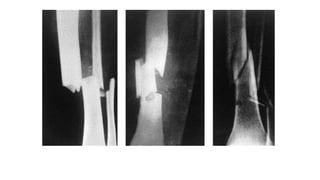

Injury • Direct force- With a direct force, the bone breaks at the point of impact; the soft tissues also are damaged • Indirect force - the bone breaks at a distance from where the force is applied

Some fracture patternssuggest the causal mechanism: (a) spiral pattern (twisting); (b) Short oblique pattern (compression); (c) triangular ‘butterfly’ fragment (bending) (d) transverse pattern (tension).